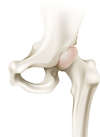

L’articulation de la hanche appelée aussi articulation coxo-fémorale met en relation la cavité articulaire du bassin (Cotyle) et la tête fémorale. Ces deux structures sont fermement emboîtées et sont entourées d’une capsule articulaire, de puissants ligaments et d’une chape musculaire. La mobilité de la tête fémorale dans le cotyle est facilité par le cartilage qui recouvre les deux surfaces osseuses et par le liquide articulaire ou synovial qui améliore le mouvement et nourrit le cartilage.

Elle possède une mobilité dans les trois plans de l’espace : d’avant en arrière (flexion/extension), latéralement (abduction/adduction), et en rotation (interne/externe). Elle est animée par des muscles parmi les plus puissants de l’organisme tels que les muscles fessiers.